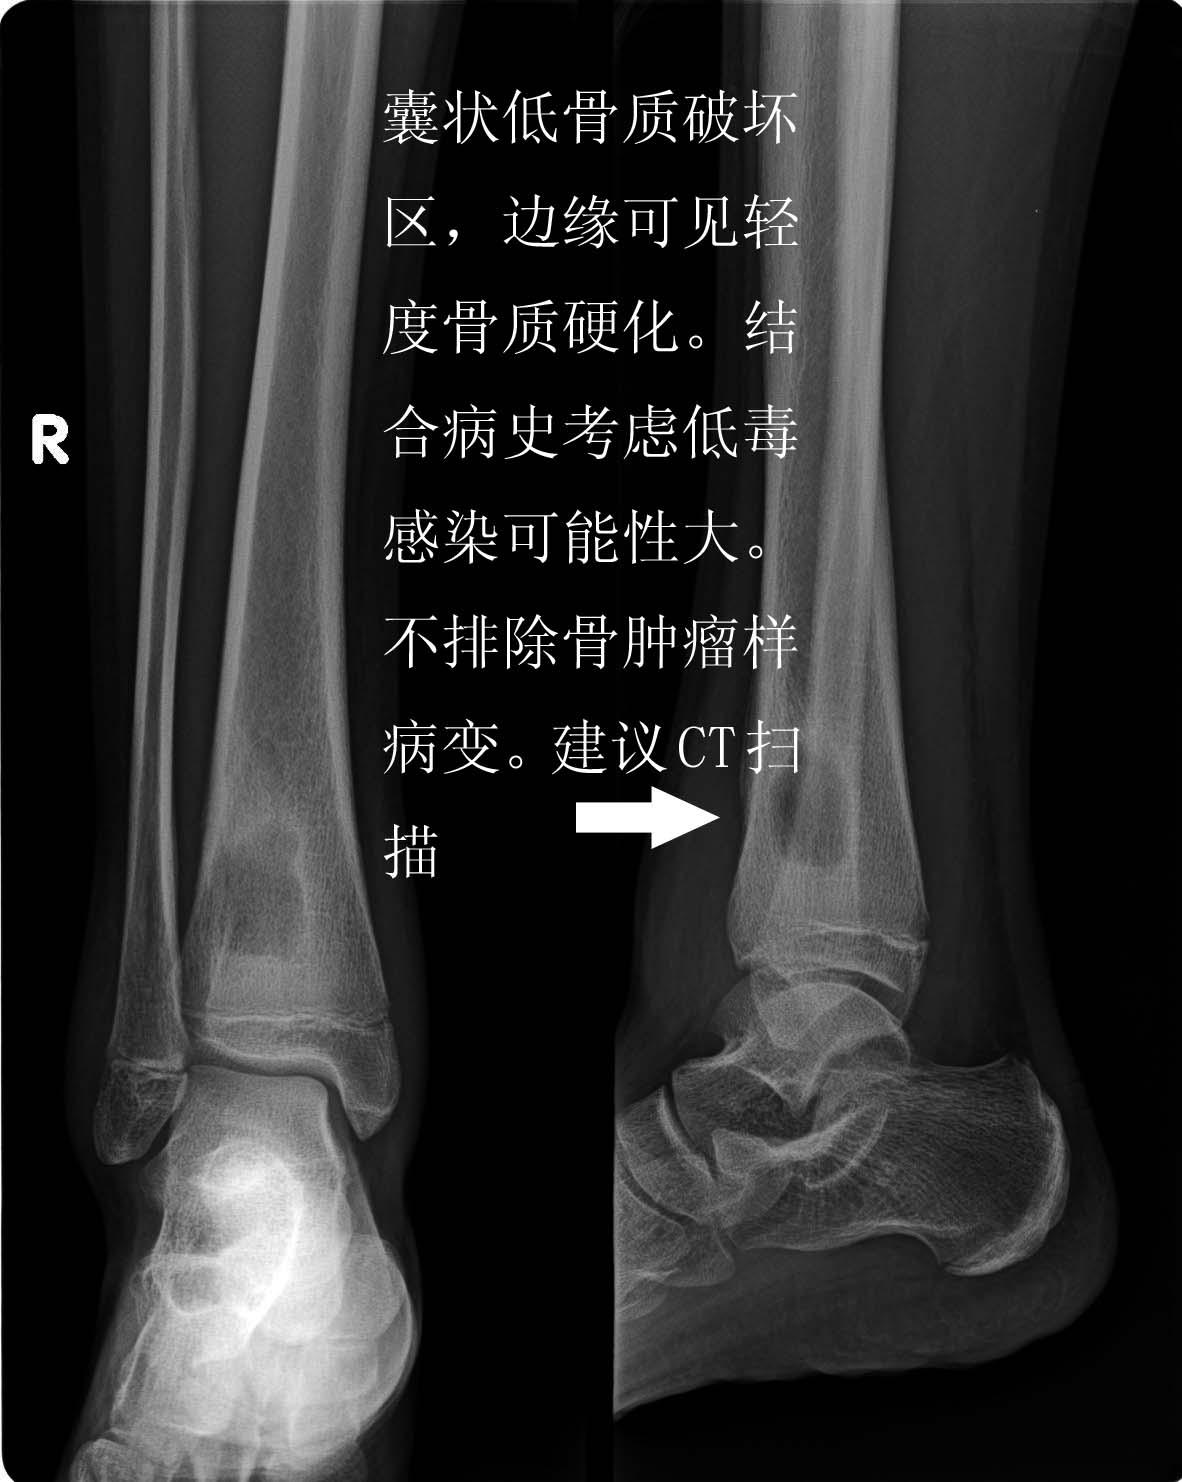

以下是引用zhangzhongshou在2007-9-1 23:10:00的发言:[br]支持brodie脓肿[br]说明:慢性骨脓肿(brodie脓肿)为相对静止的局限性感染性病灶,一般认为是低毒性化脓性感染,并与个体因素有关。多见于儿童和青年,常发生于胫腓骨上端、股骨下端、肱骨下端的干骺区。x线,骨破坏呈圆形或卵圆形,位于干骺端中央或偏一侧,病变早期破坏边缘常较模糊,周围无明显骨质硬化。随病变进展,边缘逐渐形成清晰光滑的硬化缘。周围可有反应性骨硬化。并逐渐消失于正常骨质中。骨膜反应和死骨均少见。临床症状一般比较轻微,疼痛一般多呈阵发性,持续时间短,可夜间加重。常伴有临近关节肿胀和疼痛。[br][br][本贴已被 zhangzhongshou 于 2007-9-2 0:44:05 修改过]

以下是引用hhcckk在2007-9-2 7:53:00的发言:[br]支持zhangzhongshou主任[br]支持感染[br]骨质破坏+周围有硬化边+病变未浸犯骺软骨+临床上有感染的表现